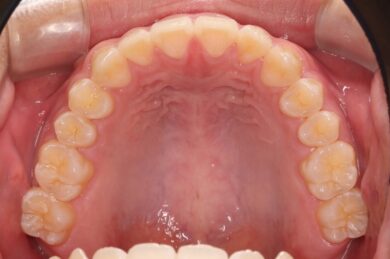

初めにマウスピース矯正「インビザライン」による術前矯正を11か月行いました。各隙間を寄せ、インプラントを埋入するスペースを確保し、適切な咬合関係を確立します。

インビザラインの治療計画では、下顎前歯がより美しく審美的に並ぶよう、ご自身の歯とインプラントの歯がほぼ同じ幅径になるよう計算し配列を行いました。

• インビザライン終了後、インプラント2本埋入2週間後